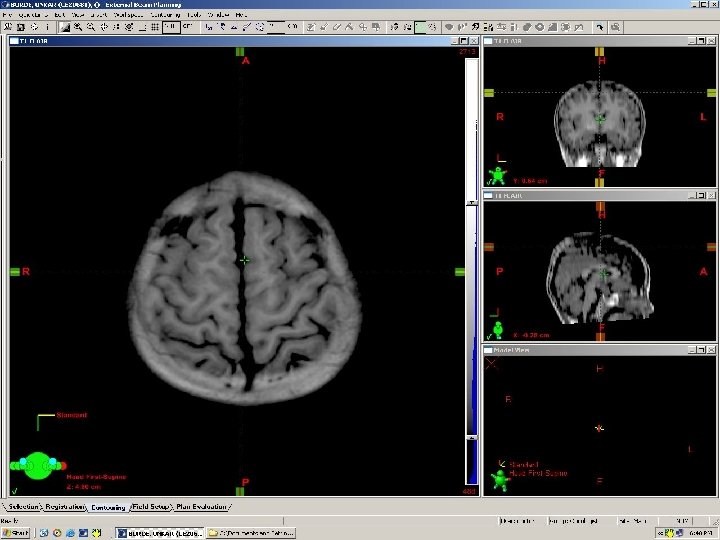

Main Sulci & Gyri

Central Cingulate Parieto Occipital

Precentral gyrus Premotor area 6 Postcentral gyrus Cingulate Superior frontal gyrus Infundibular stalk Thalamus Caudate Pineal gland Mid brain Sella 4 th ventricle Pons Inf Cerebellum medulla Spinal cord